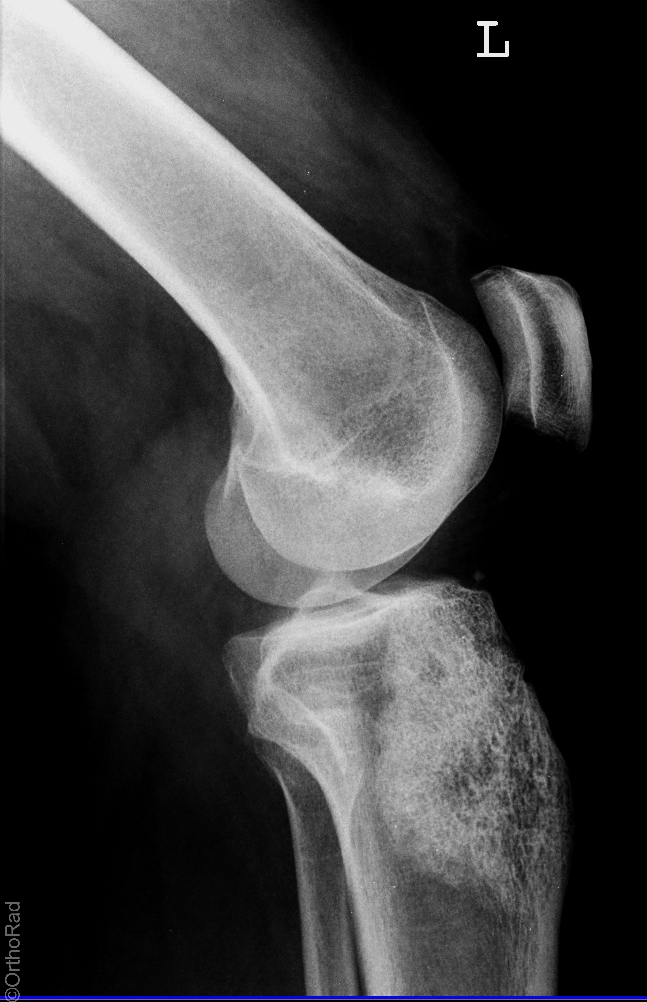

Traumatische Luxation